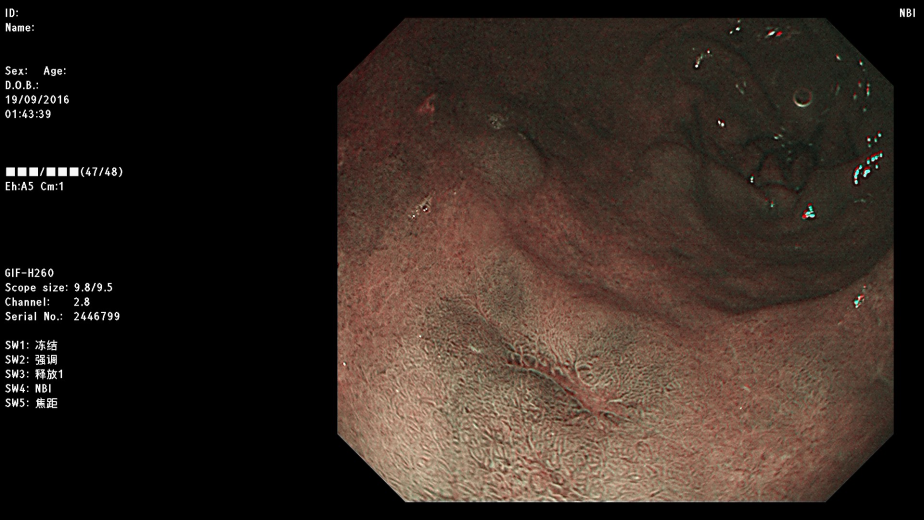

新技术胃镜所见 (有病变处显示清楚的深颜色斑片)